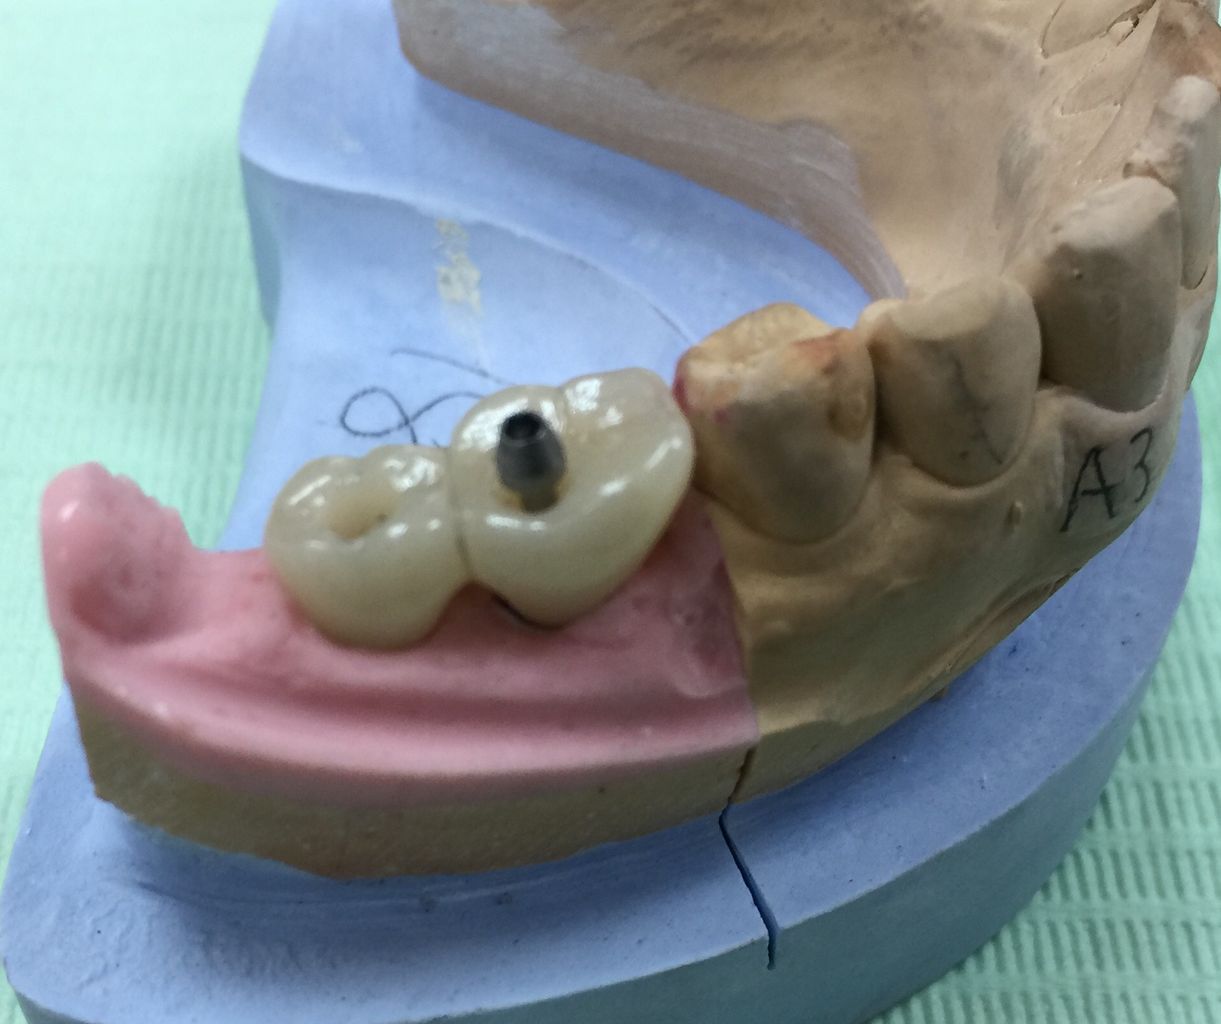

技工士さんが、コレをもとに全てがセラミックでできた被せ物を作ってくれます。

これをネジを使ってインプラントに接続します。